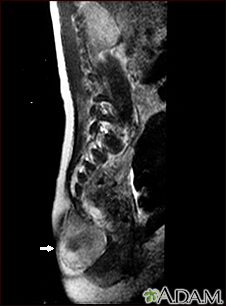

Teratoma - MRI scanBackTeratoma - MRI scanThis MRI scan shows a tumor (teratoma) at the base of the spine (seen on the left lower edge of the screen), located in the sacrum and coccyx (sacrococcygeal) area. Teratomas are present at birth and may contain hair, teeth, and other tissues. E-mail FormEmail ResultsName:Email address:Recipients Name:Recipients address:Message: